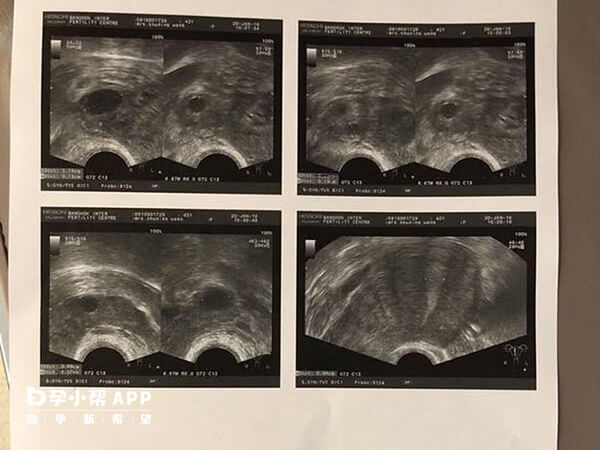

B超监测到的卵泡不一定含有成熟卵子,部分卵泡可能存在“空卵泡综合征”,即卵泡外观正常但内部无卵子,或卵子质量不佳,影响取卵结果。